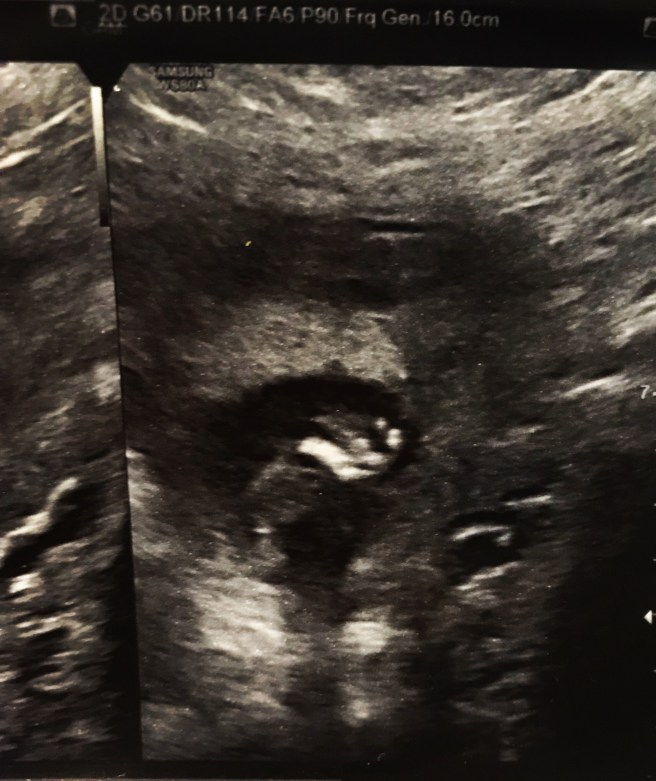

As that sweet nugget grew so did our view of her deficits. Every week we went into the office a combination of nauseating fear and pure excitement would set in. A similar dance seen in the stages of grief as well. “Yay! We get to see our girl, but what will she be like today?” At first all we could see was holoprosencephaly, which means her brain is fused together. We were told this is definitely life limiting outside of the womb. There were also issues with her facial profile and her heart but she was still too tiny (and stubborn with her wildly spirited constant movements) to see the full effect.